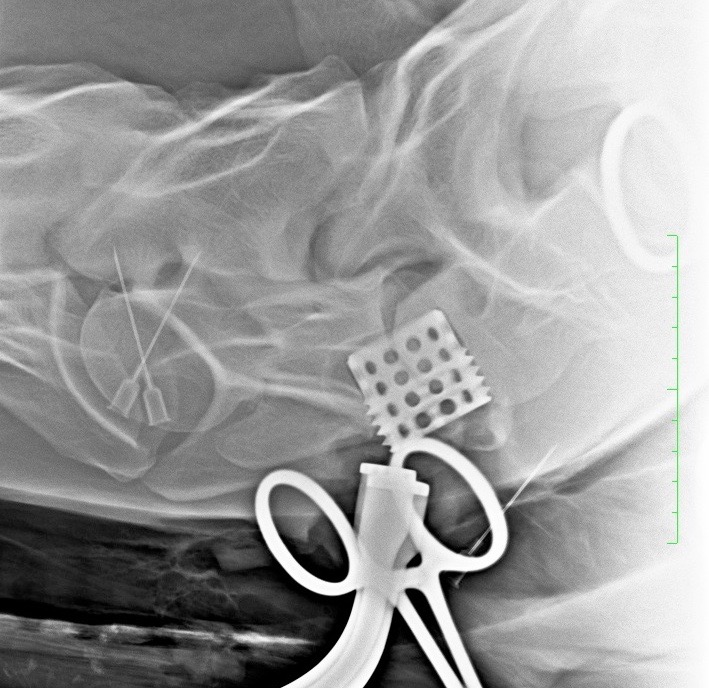

Pokud neurologické vyšetření potvrdí ataxii (stupeň 1–5), je potřeba stanovit její přesnou příčinu. Nejčastěji se jedná o zúžení páteřního kanálu v oblasti krčních obratlů, kde pak dochází k útlaku míchy – Wobblerovu syndromu. Existují ale i další příčiny ataxie, které je potřeba vzít na vědomí, například vrozené abnormality krčních obratlů (vertebrální malformace), úrazy krční páteře, nádory, virové infekce (EHV), bakteriální infekce (abscesy, záněty meziobratlových plotének a kostí) (obr. 2a, b, c), parazitární infekce nebo některé toxiny.

Obrázek 2a, b: Hříbě s ataxií a horečkou způsobenou zánětem kostí obratlů C6–C7. Na CT je jasně patrné výrazné poškození kostí v důsledku infekce (bílé šipky). Na obrázku 2b je stejný případ z jiného pohledu

Obrázek 2c: Postižená kost a meziobratlová ploténka byly chirurgicky odstraněny a oba obratle byly spojeny pomocí ploténky a šroubů